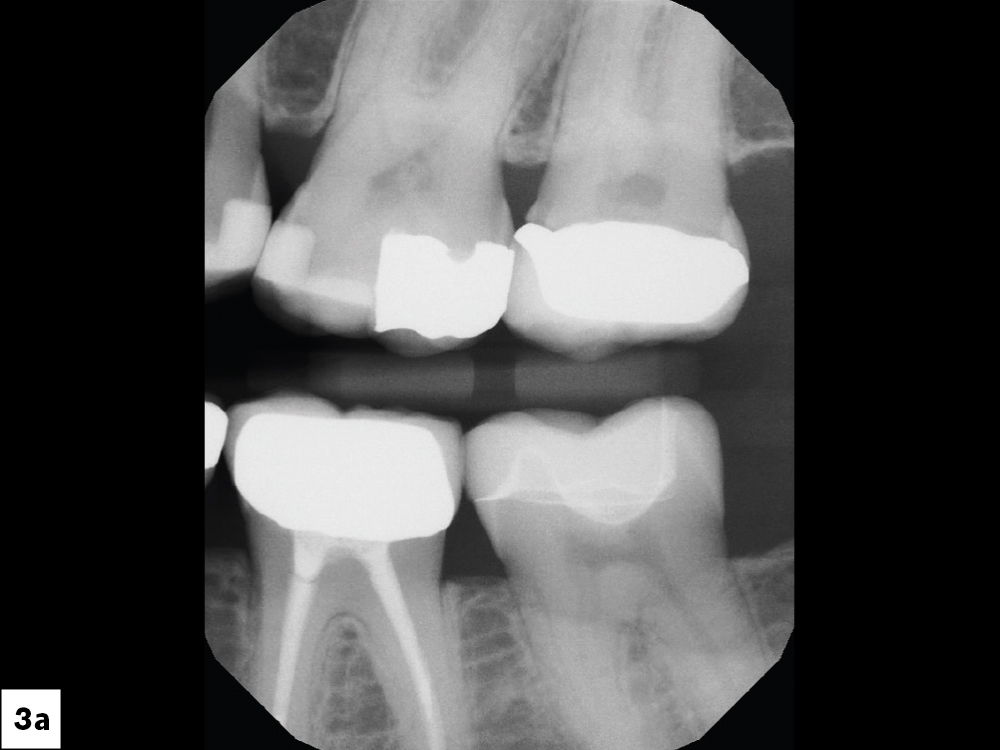

Even though she is a dental hygienist, Nikole decided to wait it out when she was told her crown on tooth #15 had an open margin. But over time, she noticed the area started to shred her floss. That’s when she decided it was time for the crown to be replaced.

Because the patient had high expectations for her restoration, I selected a BruxZir® Esthetic NOW Posterior Milling Block for its combination of esthetics and strength. Though BruxZir Esthetic was originally developed with the anterior in mind, with a yttria content that enhances the overall translucency and color, the material still maintains an excellent flexural strength of 870 MPa, meaning it is sufficiently strong enough to be used anywhere in the arch.